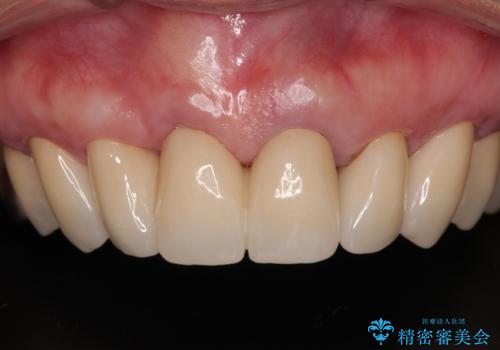

【海外から通院】統一感のない前歯をきれいに オールセラミッククラウン治療

- 歯肉ラインの段差や、歯根が黒く見えている前歯を気にして来院された患者様です。

前歯のインプラントは埋入されたポジションが望ましい位置ではなく、インプラントを活用して段差を回収することは不可能と判断し、歯肉移植によりインプラントを隠して、ブリッジにて歯肉ラインを整えることとしました。

臼歯部の治療も必要と判断されましたが、前歯部を中心とした審美領域をオールセラミッククラウンによる補綴治療を行うこととしました。

帰国時のみの治療であったため、治療期間は長くなりましたが、最小限の来院回数で、気になっていた前歯をきれいに整えることができました。